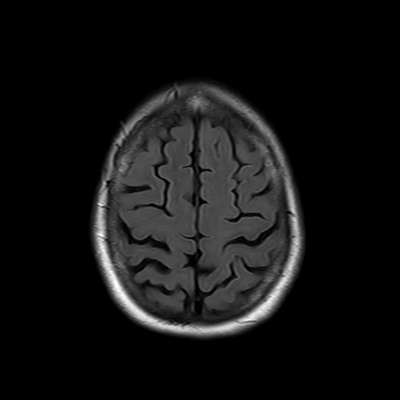

You also obtain an MRI of his brain once it's clinically safe to do so.

MRI brain (FLAIR)